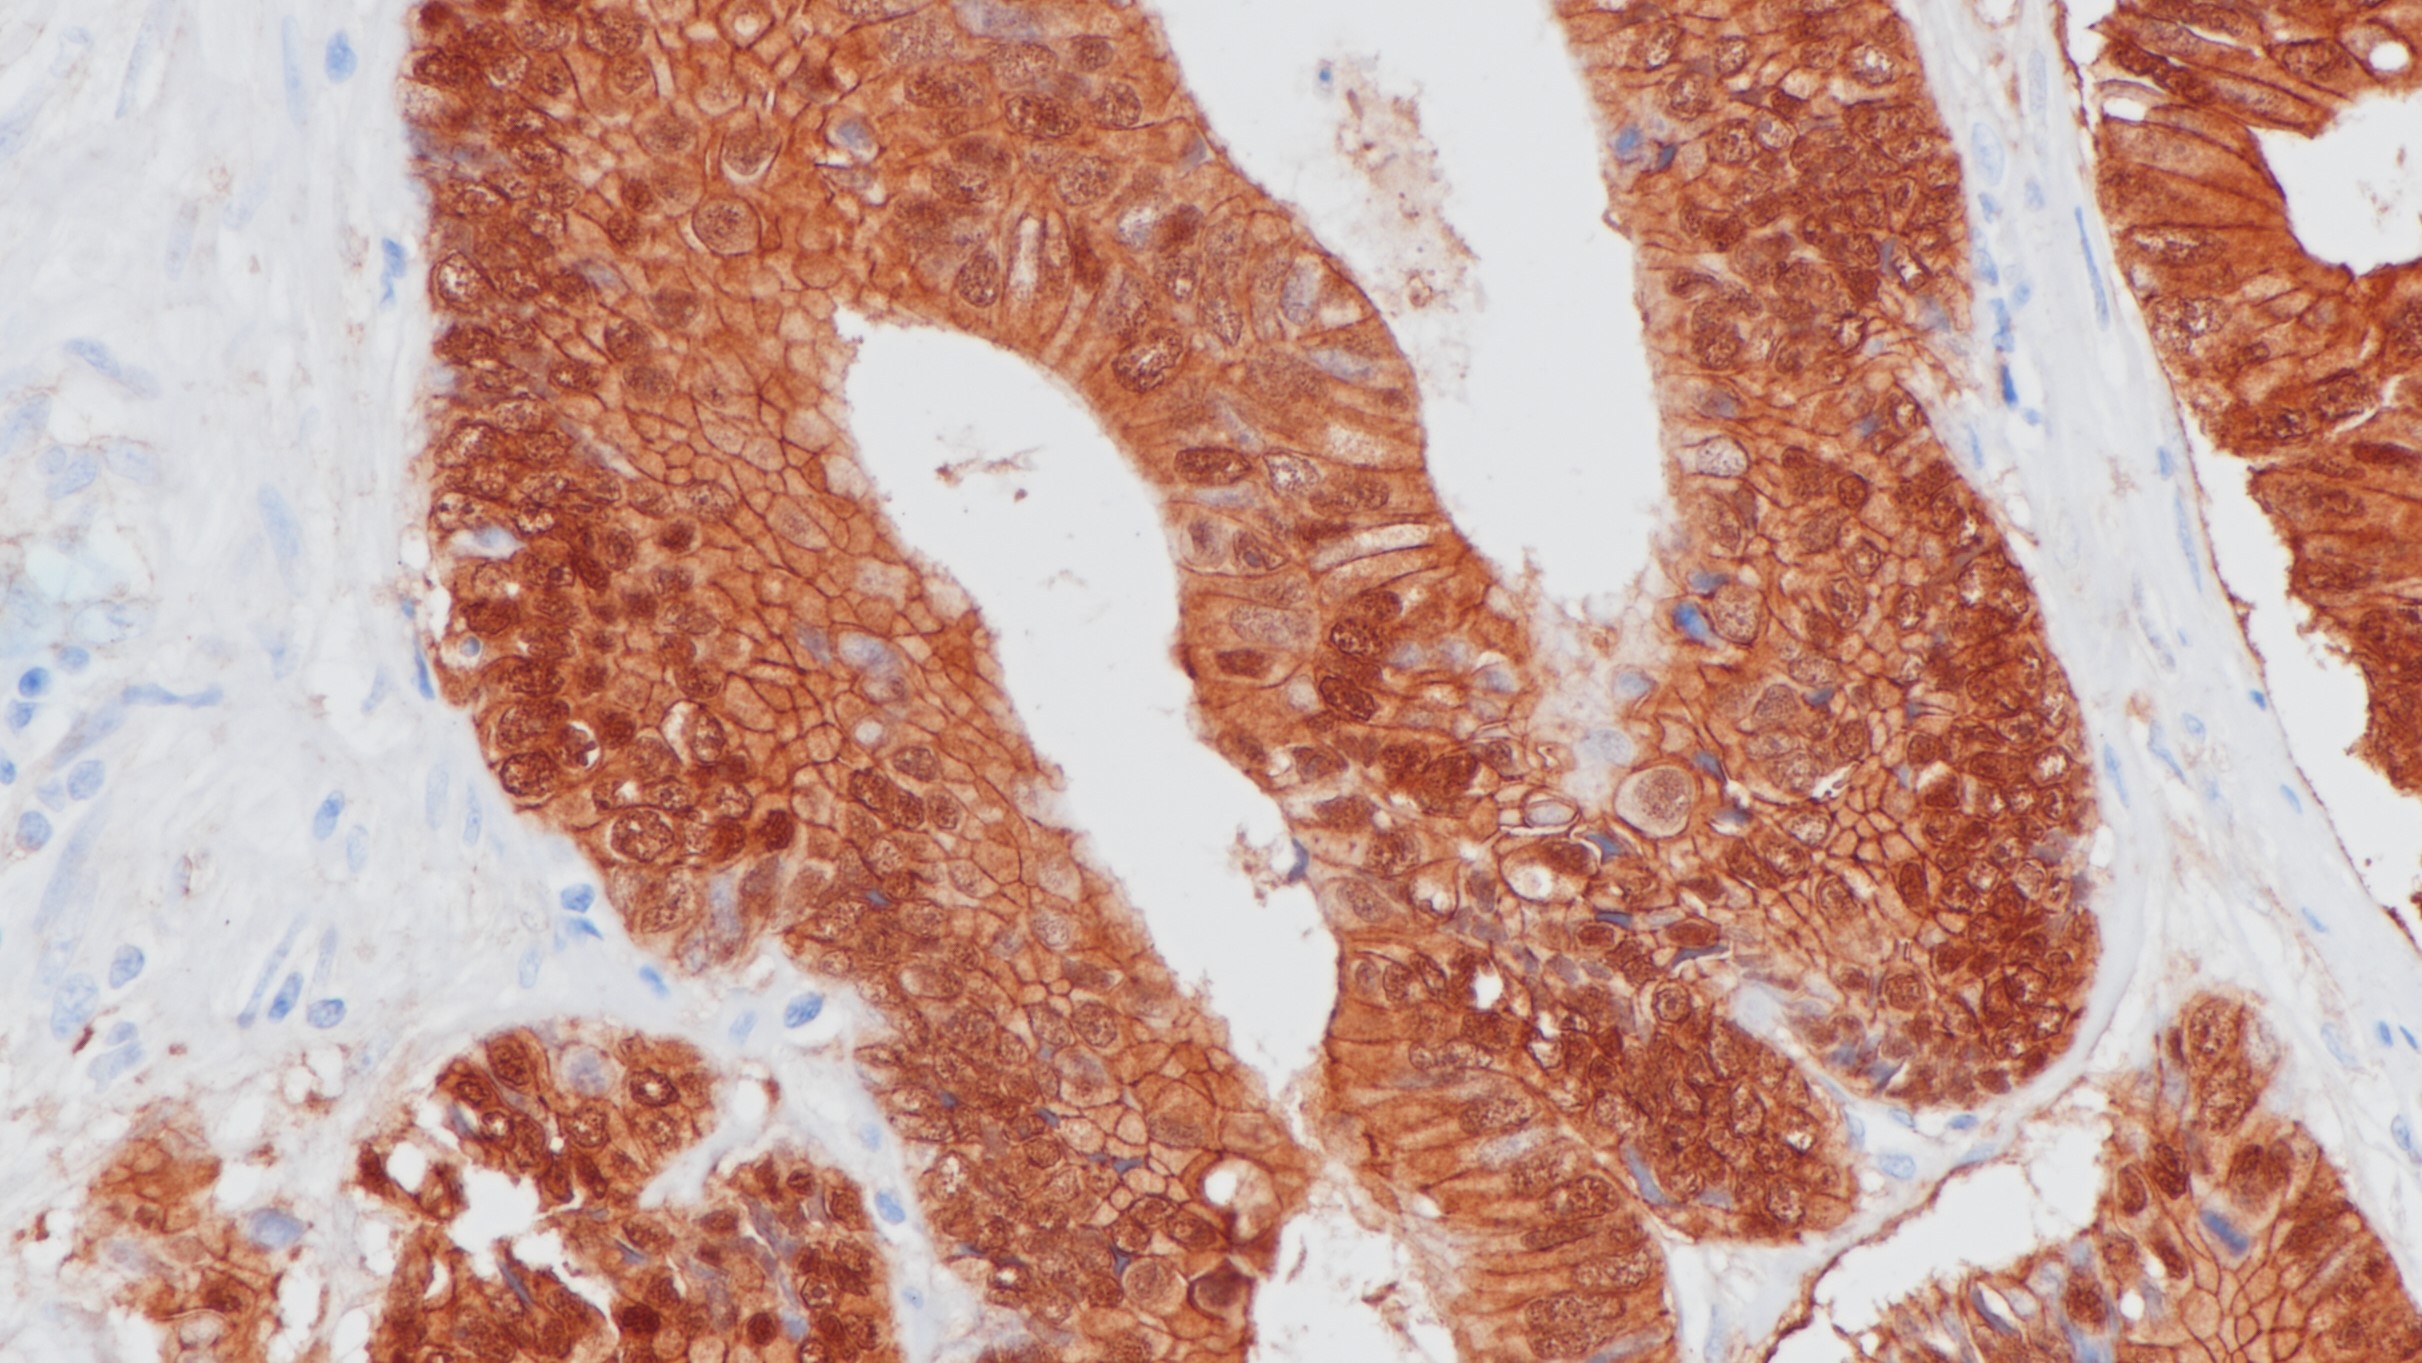

3.李秀,聂敏海,刘旭倩,谭红.E-钙粘蛋白、β-连环素和基质金属蛋白酶-7与口腔鳞状细胞癌分化程度的关系[J].西南医科大学学报,2020,43(02):124-129